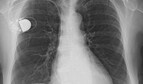

Verträgt sich das iPhone 12 mit Herzschrittmachern oder nicht? Anfang 2021 machte eine Studie, die im Heart Rhythm Journal erschien, vielen Nutzer:innen Angst. Darin hieß es, dass die Magnete im Rücken des iPhone 12 und seiner Varianten (MagSafe) Herzschrittmacher und implantierte Defibrillatoren deaktivieren könnte. Das wäre für die Patient:innen lebensbedrohlich. Apple hat empfohlen, die Geräte nicht direkt über den Implantaten zu tragen.

In seinem Support-Dokument schreibt Apple, dass Magnete im iPhone 12 und MagSafe-Zubehör „medizinische Geräte stören können“.

Die FDA hat ihre eigenen Tests durchgeführt und bestätigt frühere Studien. Eine Entwarnung sieht anders aus. Dennoch heißt es im offiziellen Schreiben der FDA, das Risiko für Patient:innen sei gering.

Die Sicherheitshinweise sind aber leicht einzuhalten: Die Geräte sollten in einem Mindestabstand von 15 Zentimetern zum Implantat am Körper getragen werden. In Zukunft könnten immer mehr Geräte mit entsprechenden Funktionen in Umlauf kommen, warnt die Behörde. Träger:innen von Implantaten sollten also etwas Vorsicht walten lassen, wo sie die Geräte am Körper beziehungsweise in der Kleidung tragen. Wir leiten für uns daraus den Schluss ab, dass es besser ist, die Smartphones wie üblich in der Hosentasche oder der Jackentasche zu transportieren aber nicht in Brusttaschen. Natürlich gibt es auch Implantate, die an anderen Stellen getragen werden – wie zum Beispiel Insulinpumpen. Dazu gibt es von der FDA aber keine Hinweise.